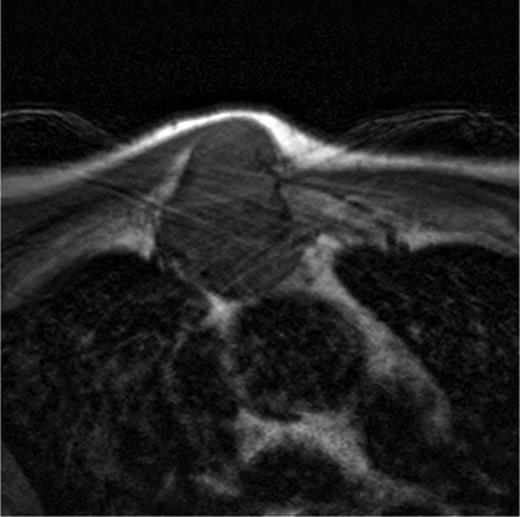

A 60-year-old male patient presented himself to the outpatient clinic of our department with a progressive sternal mass. An MRI scan indicated a tumour involving the manubrium extending to the first and second ribs and involving the right clavicle and sternoclavicular joint (Figs 1 and 2). Based on radiological evaluation, a core biopsy was obtained and a low-grade chondrosarcoma was characterized. Radiological evaluation indicated primary tumour resection to be the treatment of choice. Radical excision of the tumour was performed and resulted in resection of the manubrium, as well as the medial third of the right clavicle and the right first and second ribs. Steel wires through the sternum and left sternoclavicular joint spanned the 6.5 cm sternal defect (Figs 3 and 4) and a polypropylene mesh filled with methyl methacrylate composite (Surgical Simplex®), Howmedica Osteonics, Limerick, Ireland, was placed, yielding a stable reconstruction of the sternal defect (Figs 5–8). The sternocleidomatoideus muscle was re-inserted to the polypropylene mesh. Pathological examination showed complete excision of the tumour. The patient recovered uneventfully and was discharged 7 days post-operatively. At seven year follow-up, the patient displayed excellent functional and aesthetic results. Optimal function of his shoulders allowed a complete return to work and other activities without disabilities.

A MRI scan of a patient showing a tumour involving the manubrium extended to the first and second ribs including the right clavicle and sternoclavicular joint.